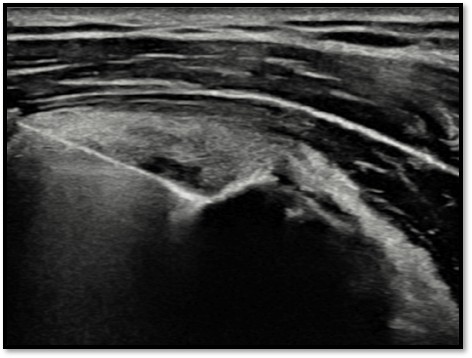

MRI와 초음파를 다시 검토했습니다.

회전근개 극상건의 관절면측(articular-side) 부분파열.

Step 6: 확인 및 마무리

초음파로 봉합 상태를 확인하고 마무리합니다.

봉합 부위 안정성 확인